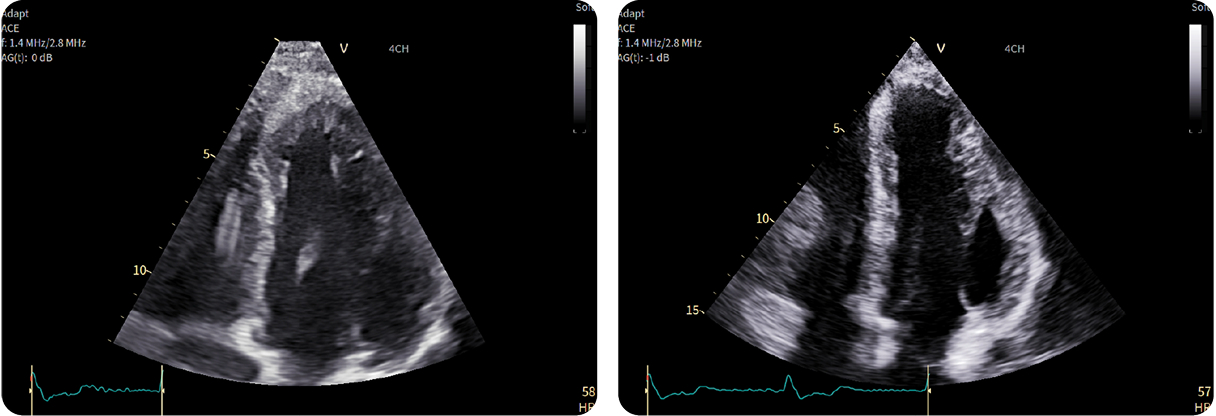

Caso condiviso da Marcello De Santis